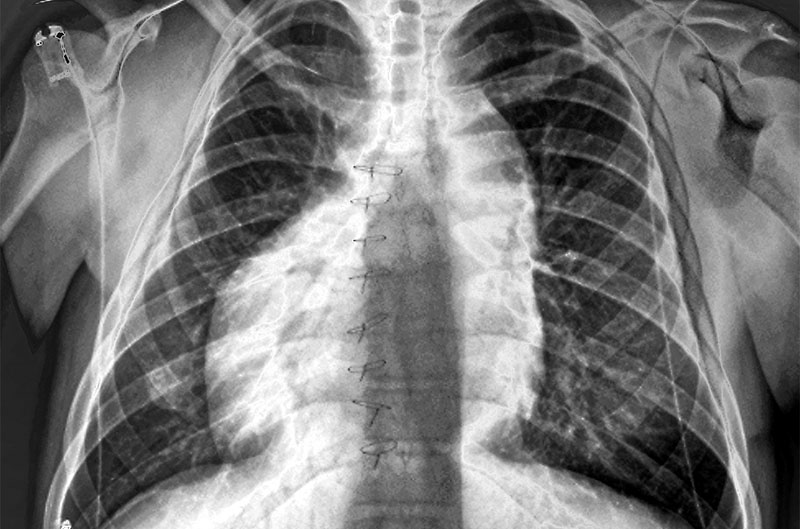

मनुष्यों की बात करें तो हर 10 हज़ार में से एक व्यक्ति गलत जगह स्थित अंगों के साथ पैदा होता है। इसे हेटेरोटैक्सी कहते हैं। रेवरसेड की टीम ने हेटेरोटैक्सी से ग्रस्त 183 लोगों के सिरॉप जीन का अनुक्रमण किया और उन्हें 12 परिवारों के 21 व्यक्तियों में सिरॉप में उत्परिवर्तन देखने को मिले। वैसे सिरॉप की खोज से इस समस्या का इलाज करने में कोई मदद शायद न मिले लेकिन यह महत्वपूर्ण तो है ही। शोधकर्ताओं को कुछ अंदाज़ तो है कि यह जीन सममिति को कैसे तोड़ता है लेकिन वे और अध्ययन करना चाहते हैं। (स्रोत फीचर्स)